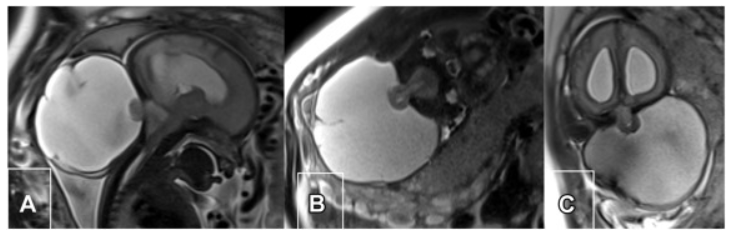

有个患者大概半年前开始觉得后背隐隐作痛,偶尔右手手指发麻,没当回事,以为是颈椎病或者睡觉压到了。后来麻木感越来越明显才去拍了个核磁,报告上写的是椎管内占位,考虑脊膜瘤。...

更新时间:2026-05-14 14:04:38